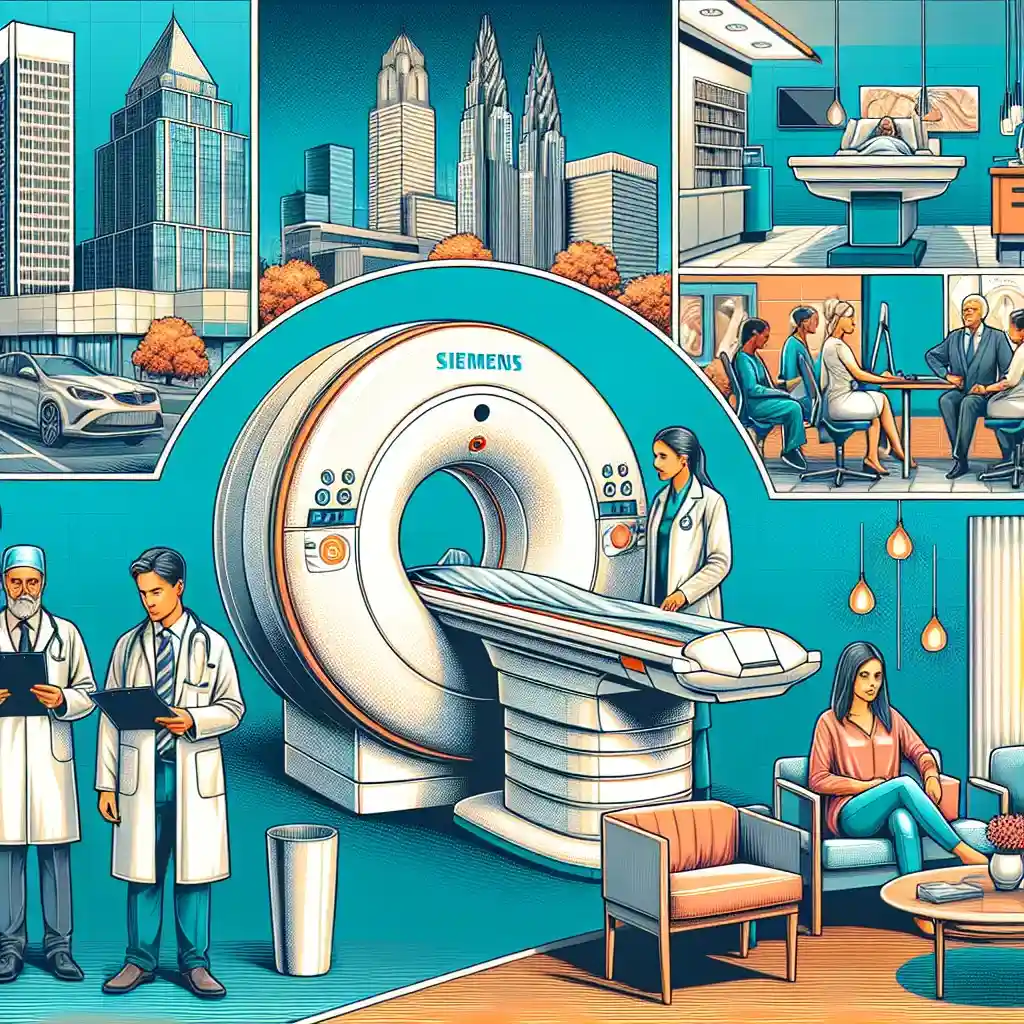

Если вам необходимо пройти МРТ головы в Кривом Роге, важно выбрать надежное медицинское учреждение, которое обеспечит точную диагностику. Магнитно-резонансная томография – это высокоточный метод обследования мозга, который помогает выявить различные патологии. В нашей статье вы найдете информацию о лучших клиниках Кривого Рога, стоимости процедуры, а также о МРТ с контрастом и отзывах пациентов. Сделайте осознанный выбор для своего здоровья!

В Кривом Роге эти клиники считаются одними из лучших, обеспечивая высокий уровень сервиса и современное оборудование. Процедура МРТ головы является неинвазивной и безболезненной, что делает ее доступной и удобной для широкого круга пациентов. Точная диагностика позволяет своевременно выявить даже самые сложные заболевания головного мозга, обеспечивая эффективное лечение.